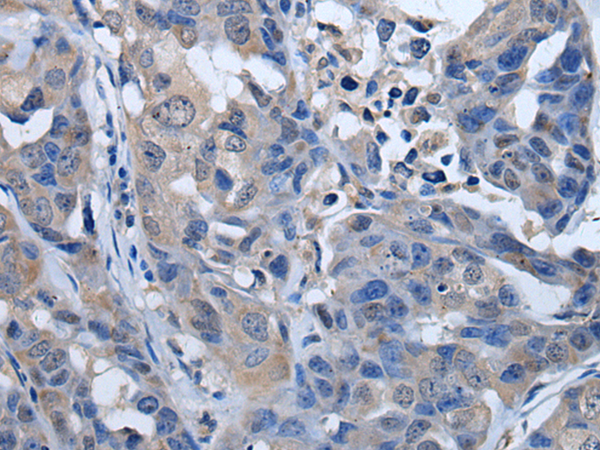

分类: 科研抗体货号: P08635别名: RP-C; PP2Ac; PP2CA; PP2Calpha应用: WB,IHC反应种属: Human, Mouse, Rat

分类: 科研抗体货号: P08648别名: S4; p56; P26S4应用: WB,IHC反应种属: Human, Mouse, Rat